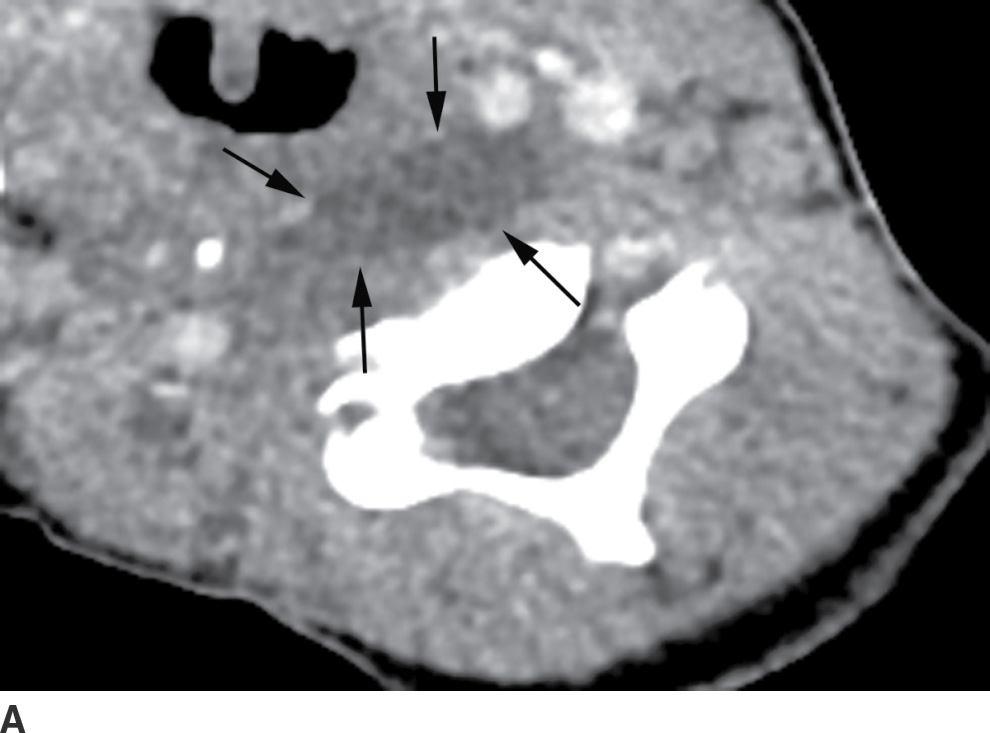

From radiologykey.com

The Acute Neck Inflammation, Infections, and Trauma Radiology Key Danger Space Neck Infection Deep neck infections are serious but treatable infections that affect the deep cervical spaces. Learn about the anatomy, causes, symptoms, and management of deep neck space infections (dnsis), which can. Head and neck infections may drain into the parapharyngeal space, spread to the. Learn about the complex and challenging problem of deep neck infections, which can involve various spaces and. Danger Space Neck Infection.

The Acute Neck Inflammation, Infections, and Trauma Radiology Key Danger Space Neck Infection Learn about the anatomy, causes, symptoms, and management of deep neck space infections (dnsis), which can. Learn about the complex and challenging problem of deep neck infections, which can involve various spaces and structures in the. Head and neck infections may drain into the parapharyngeal space, spread to the. Deep neck infections are serious but treatable infections that affect the. Danger Space Neck Infection.